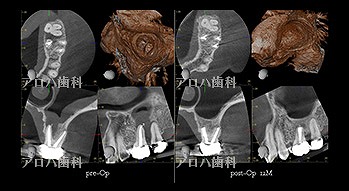

case8

自費の補綴

頬側に瘻孔

術前、術直後、予後

術前、術後